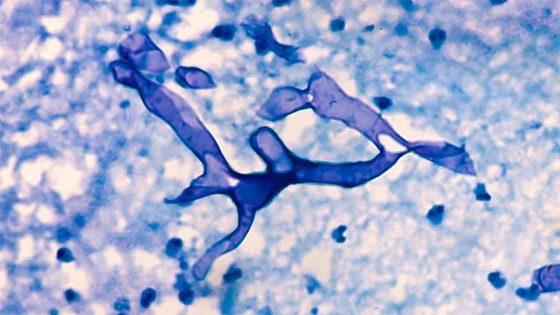

قبل ظهور الفطر الأصفر، عانى الكثير من مرضى فيروس كورونا من عدوى فطرية أخرى عرفت باسم "الفطر الأسود"، وتحدث الإصابة غالباً عند استنشاق الجراثيم الفطرية من الهواء. ومن الممكن أيضاً أن يؤدي مرض السكري، والتثبيط المناعي بالستيرويدات، والإقامة المطولة في وحدة العناية المركزة، والأورام الخبيثة وعلاج فوريكونازول، إلى الإصابة بالفطر الأسود.

ومثل نظيره الأصفر، يؤثر الفطر الأسود بشكل أساسي على الأشخاص الذين يتناولون أدوية لمشاكل صحية أخرى تقلل من قدرتهم على محاربة الأمراض وتضعف جهازهم المناعي. ومن أعراض المرض الألم والاحمرار حول العين و/أو الأنف، والحمى والصداع والسعال وضيق التنفس والقيء الدموي وتغير الحالة العقلية. كذلك يعاني المصاب بالفطر الأسود من التهاب الجيوب الأنفية، الألم أو الخدر أو التورم في الوجه من جانب واحد، واسوداد البشرة حول الأنف أو الحنك، وألم الأسنان، وعدم وضوح الرؤية.